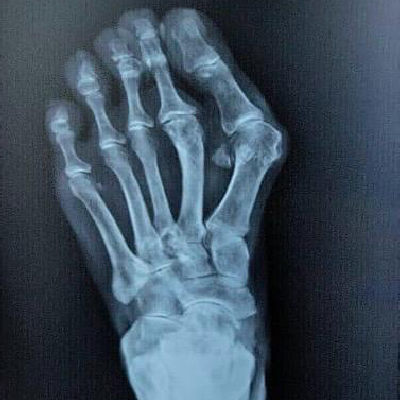

Minimally Invasive Surgery (MIS) :